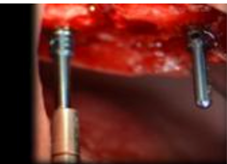

Lateral window in two times: Best-documented procedure, showing long-term implant survival rates. This technique can be applied in the most diverse clinical situations, except when there are local and general contraindications for oral surgeries.

Lateral window in one time: The literature supports this procedure with implant long-term survival rates similar to the lateral window in two times technique. There is not enough scientific evidence to reach a consensus regarding a minimum bone height. To achieve good primary stability, the following minimum measures may be suggested for the subantral bone tissue: 3 mm in height and 5 mm wide9. This primary stability depends not only on quantity but also on implant quality, technique and design. Some studies show that rough surfaces have a better survival rate than machined implants10.

Crestal approach technique: Summers technique. Osteotomy is performed for the implant up to 1mm subantrally, until the sinus floor is reached with osteotomes, allowing for increases in height of 2 to 5 mm. This technique also shows high survival rates, similar to the traditional technique11. A minimum height of 5 mm of residual bone is recommended9. A problem with this technique is that the perforation of the membrane may go unnoticed, so placing bone substitutes is recommended11.